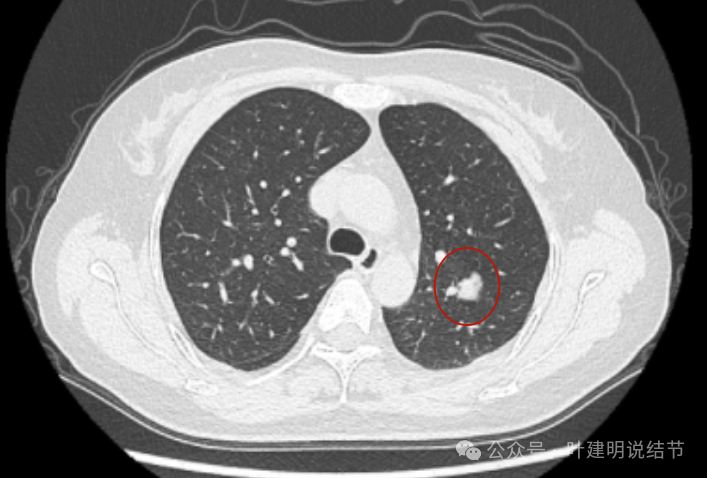

2024年10月,病灶较2019年时明显显得大了一些,挨着邻近血管了。

2023年12月,与血管已经贴着了。整体较最早时大了不少。

纵隔窗增强见血管与病灶没有间隙,病灶内部密度不均。